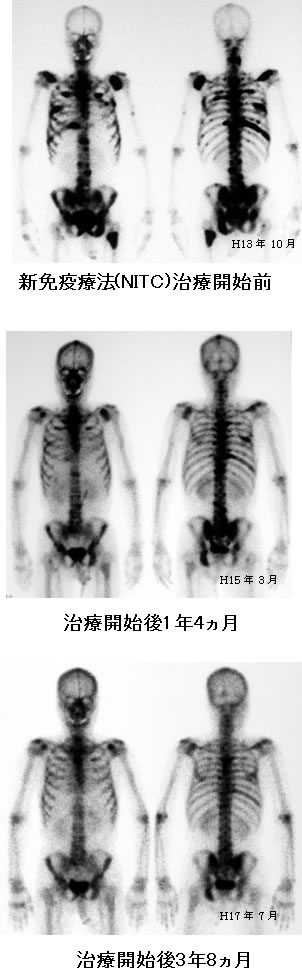

今年8月に前立腺癌の生検を受け10本中1本陽性でした グリソンスコア6psa155でした 9月骨シンチを受け1箇所集積があるとの事ただし1箇所である事と呼称は忘れましたがマーカーのような数字が0から1までの間で034と. 骨シンチ 40程に改善 足の痛み違和感ほぼ消える 身体に不都合何もなし 平成12年 4月 psa 05 骨シンチ 腰椎骨盤以外はほぼ消えた 左足は椅子に座っているとしびれの様なものを感じる程度 平成12年.

前立腺 癌 骨シンチ. 外部サイトへ whats 前立腺がんを離れます リンク先の第三者のサイトについてのお問い合わせはそれぞれのお問い合わせ先にご連絡くださいwhats前立腺がんはその第三者のサイトの内容等についての責任は負いかねますのでご了承ください. 平成17年3月の人間ドックで前立腺癌が疑われ当時49歳その年の8月に前立腺癌が発見され 9月28日に前立腺癌の手術を受けました当時50歳 前立腺癌はpsa 検査をすることにより確実に早期発見のできる癌ですがその年に私がpsa 検査を受けたのはたまたまその年の検査項目にpsa. 骨シンチで転移したところが真っ黒になっているのを見たときは痛かったが今はホルモン療法でpsaも下がり痛くないので放射線治療は受けないことにした前立腺がんの語り 認定npo法人 健康と病いの語り ディペックス.

前立腺がんの症状 がん治療に免疫の力をプラス がん免疫療法情報ガイド